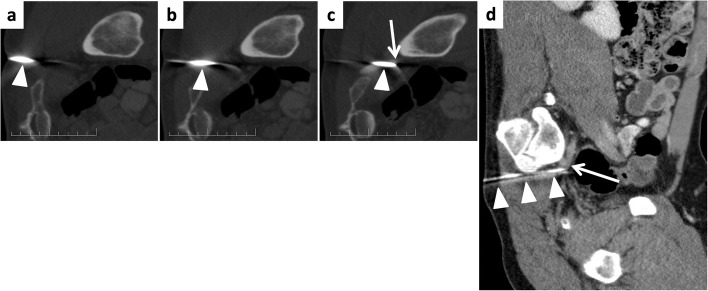

Background: Iatrogenic superior gluteal artery injury (SGA) following bone marrow biopsy is rare but potentially life-threatening. Due to the deep intrapelvic location of the vessel, conventional management with manual compression or surgical repair is challenging. Traditional management via endovascular coil embolization requires arterial access and vessel sacrifice. Case presentation We present a case of SGA injury resulting from a bone marrow biopsy in a patient with suspected T-cell lymphoma. The injury was successfully managed using a 6 french Angioseal closure device applied directly through the biopsy puncture site in the gluteal region, with the patient maintained in the lateral decubitus position. The approach achieved immediate hemostasis while preserving arterial patency.

Conclusion: This represents the first reported use of an Angioseal device for direct percutaneous treatment of iatrogenic SGA injury. This technique offers an effective hemostasis and vessel preservation, expanding the interventional radiology's armamentarium.